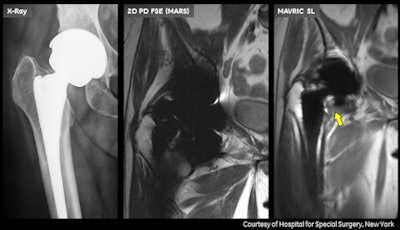

First shown at the RSNA 2011 meeting, MAVRIC SL uses an algorithm that reduces image distortion in the regions near MR-conditional metal implants, enabling physicians to see tissue surrounding an implant to help them with diagnosis, according to the company.

The announcement came on the same day as the release of a study from the Hospital for Special Surgery. Researchers found that MRI can detect inflammation of the joint lining, known as synovitis, in patients with metal-on-metal hip implants long before symptoms appear, allowing for a more conclusive diagnosis and effective planning for follow-up care (Journal of Bone & Joint Surgery, May 15, 2013, Vol. 95:10, pp. 895-902).

"MRI can be used as a screening tool to distinguish those patients with an adverse local tissue reaction," said Dr. Hollis Potter, chief of the division of MRI at the Hospital for Special Surgery. "We also have shown it is the most accurate means by which to assess wear-induced bone loss."

Even in asymptomatic patients, MAVRIC SL technology can recognize an issue that needs to be monitored, Potter said, providing clinical information for an issue that can have significant human and economic costs, particularly when diagnosis is delayed.